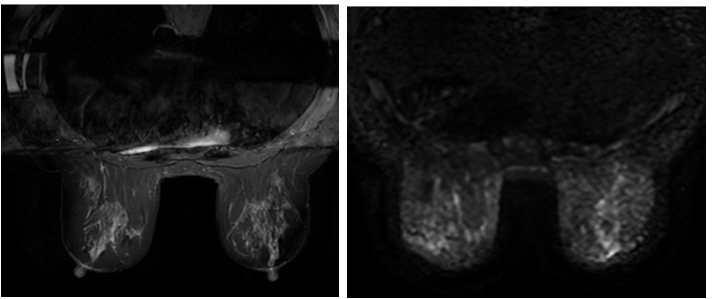

Sau 1 chu kỳ, bệnh nhân được chụp MRI đánh giá kiểm tra lại:

MRI tuyến vú trái (10/9/2024): Vị trí 11h cách núm vú khoảng 2cm có nốt bờ tua gai không đều, tăng nhẹ tín hiệu trên T2W, giảm tín hiệu trên T1W, hạn chế khuếch tán, ngấm thuốc sớm và mạnh sau tiêm, có thải thuốc một phần, xung quanh có các nốt nhỏ đường kính khoảng 6mm và các dải ngấm thuốc tính chất tương tự, tổn thương tạo thành đám kích thước 38x42mm, không thấy xâm lấn cơ thành ngực và da vú lân cận. (BIRADS 6)